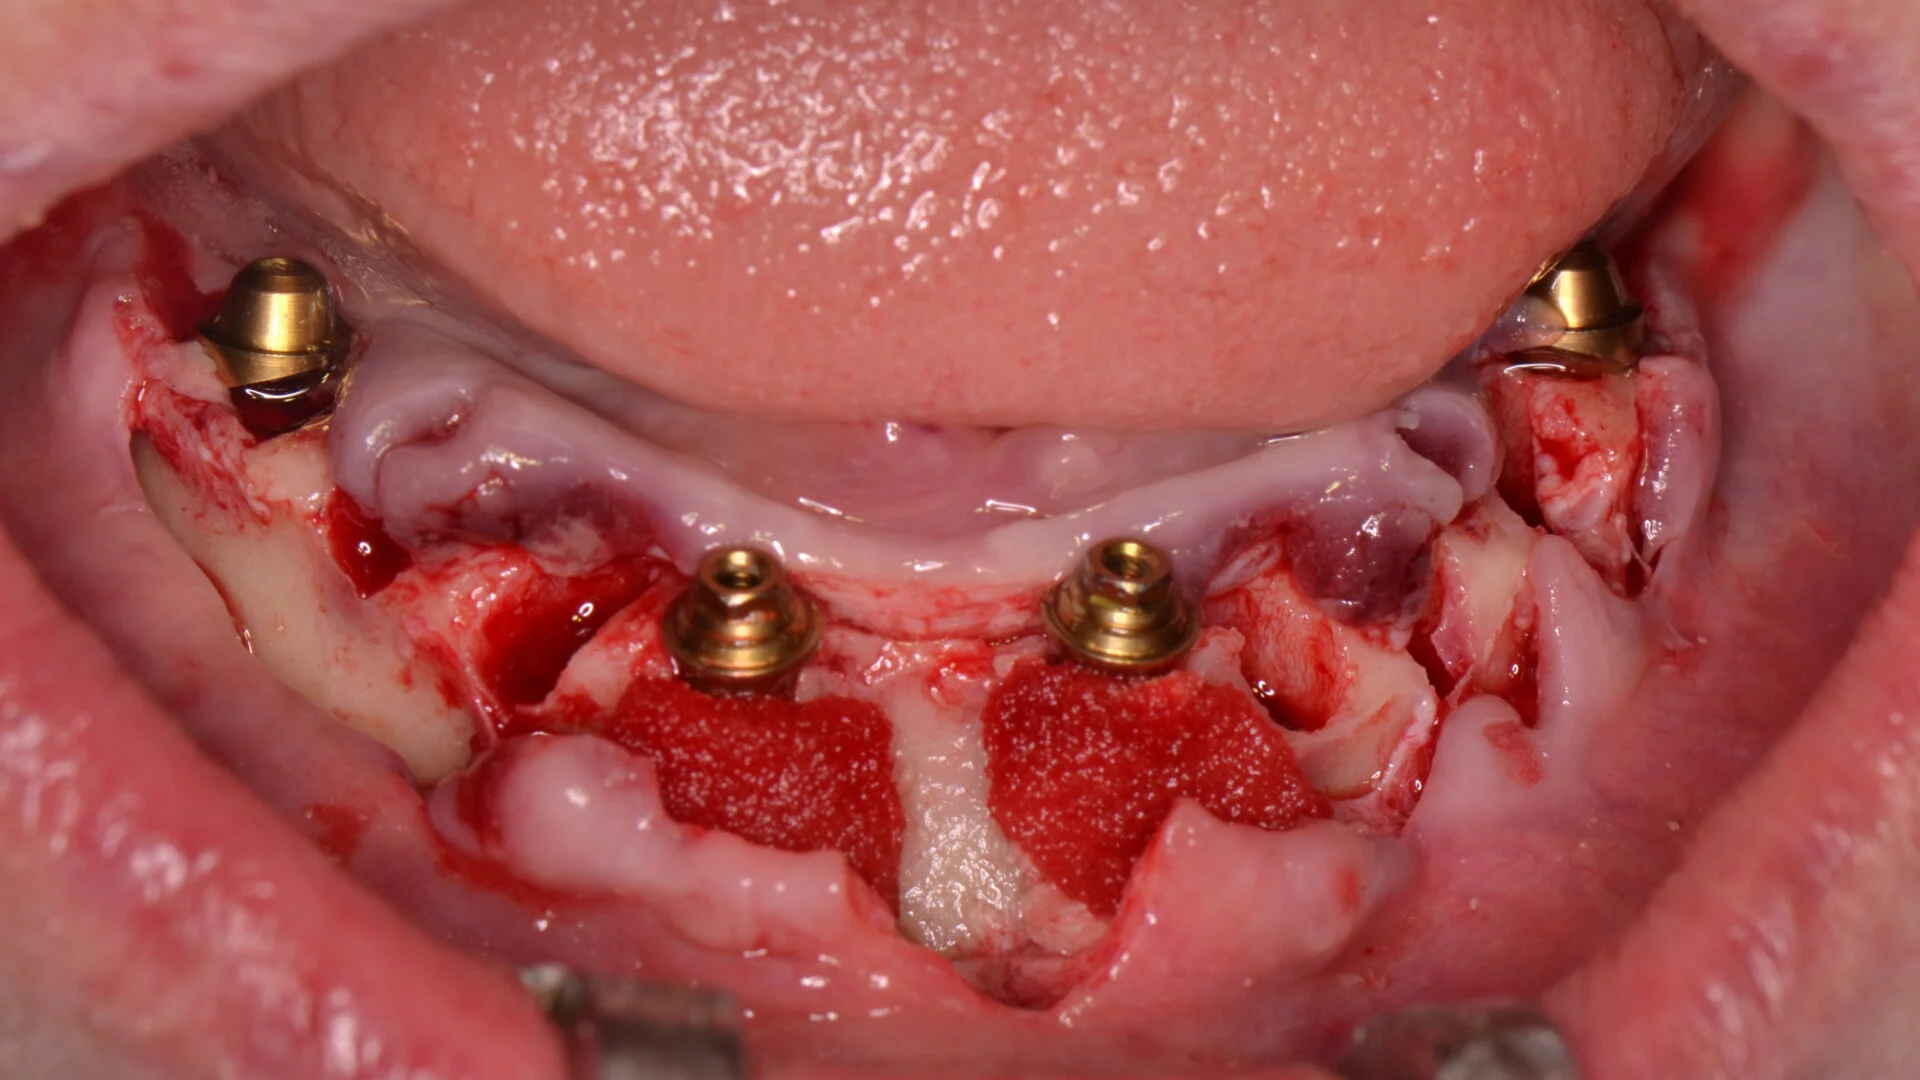

Manejo Clínico basado en evidencia científica actualizada, manejo de tejidos blandos y aplicación de la última tecnología disponible para planificación y ejecución de la Implantología.

Formar cirujanos dentistas especialistas en Implantología Bucomaxilofacial, competentes para diagnosticar, tratar y establecer el pronóstico de problemas de rehabilitación oral en pacientes desdentados totales y parciales. Esta formación se basa en la mejor evidencia científica disponible, principios éticos sólidos y una actitud orientada al aprendizaje continuo.

2. Desarrollar competencias clínicas para diagnosticar, planificar, ejecutar y controlar tratamientos quirúrgicos y protésicos en implantología, priorizando el bienestar del paciente y el impacto positivo en la comunidad.

• 58% se destinan a práctica clínica con tutoría directa.

Las asignaturas están diseñadas para cumplir con los objetivos formativos y el perfil de egreso del programa, asegurando una sólida preparación teórico-práctica. Esta formación permite al especialista diagnosticar, planificar y ejecutar acciones clínicas orientados a la rehabilitación oral de pacientes desdentados mediante el uso de implantes óseo-integrables.